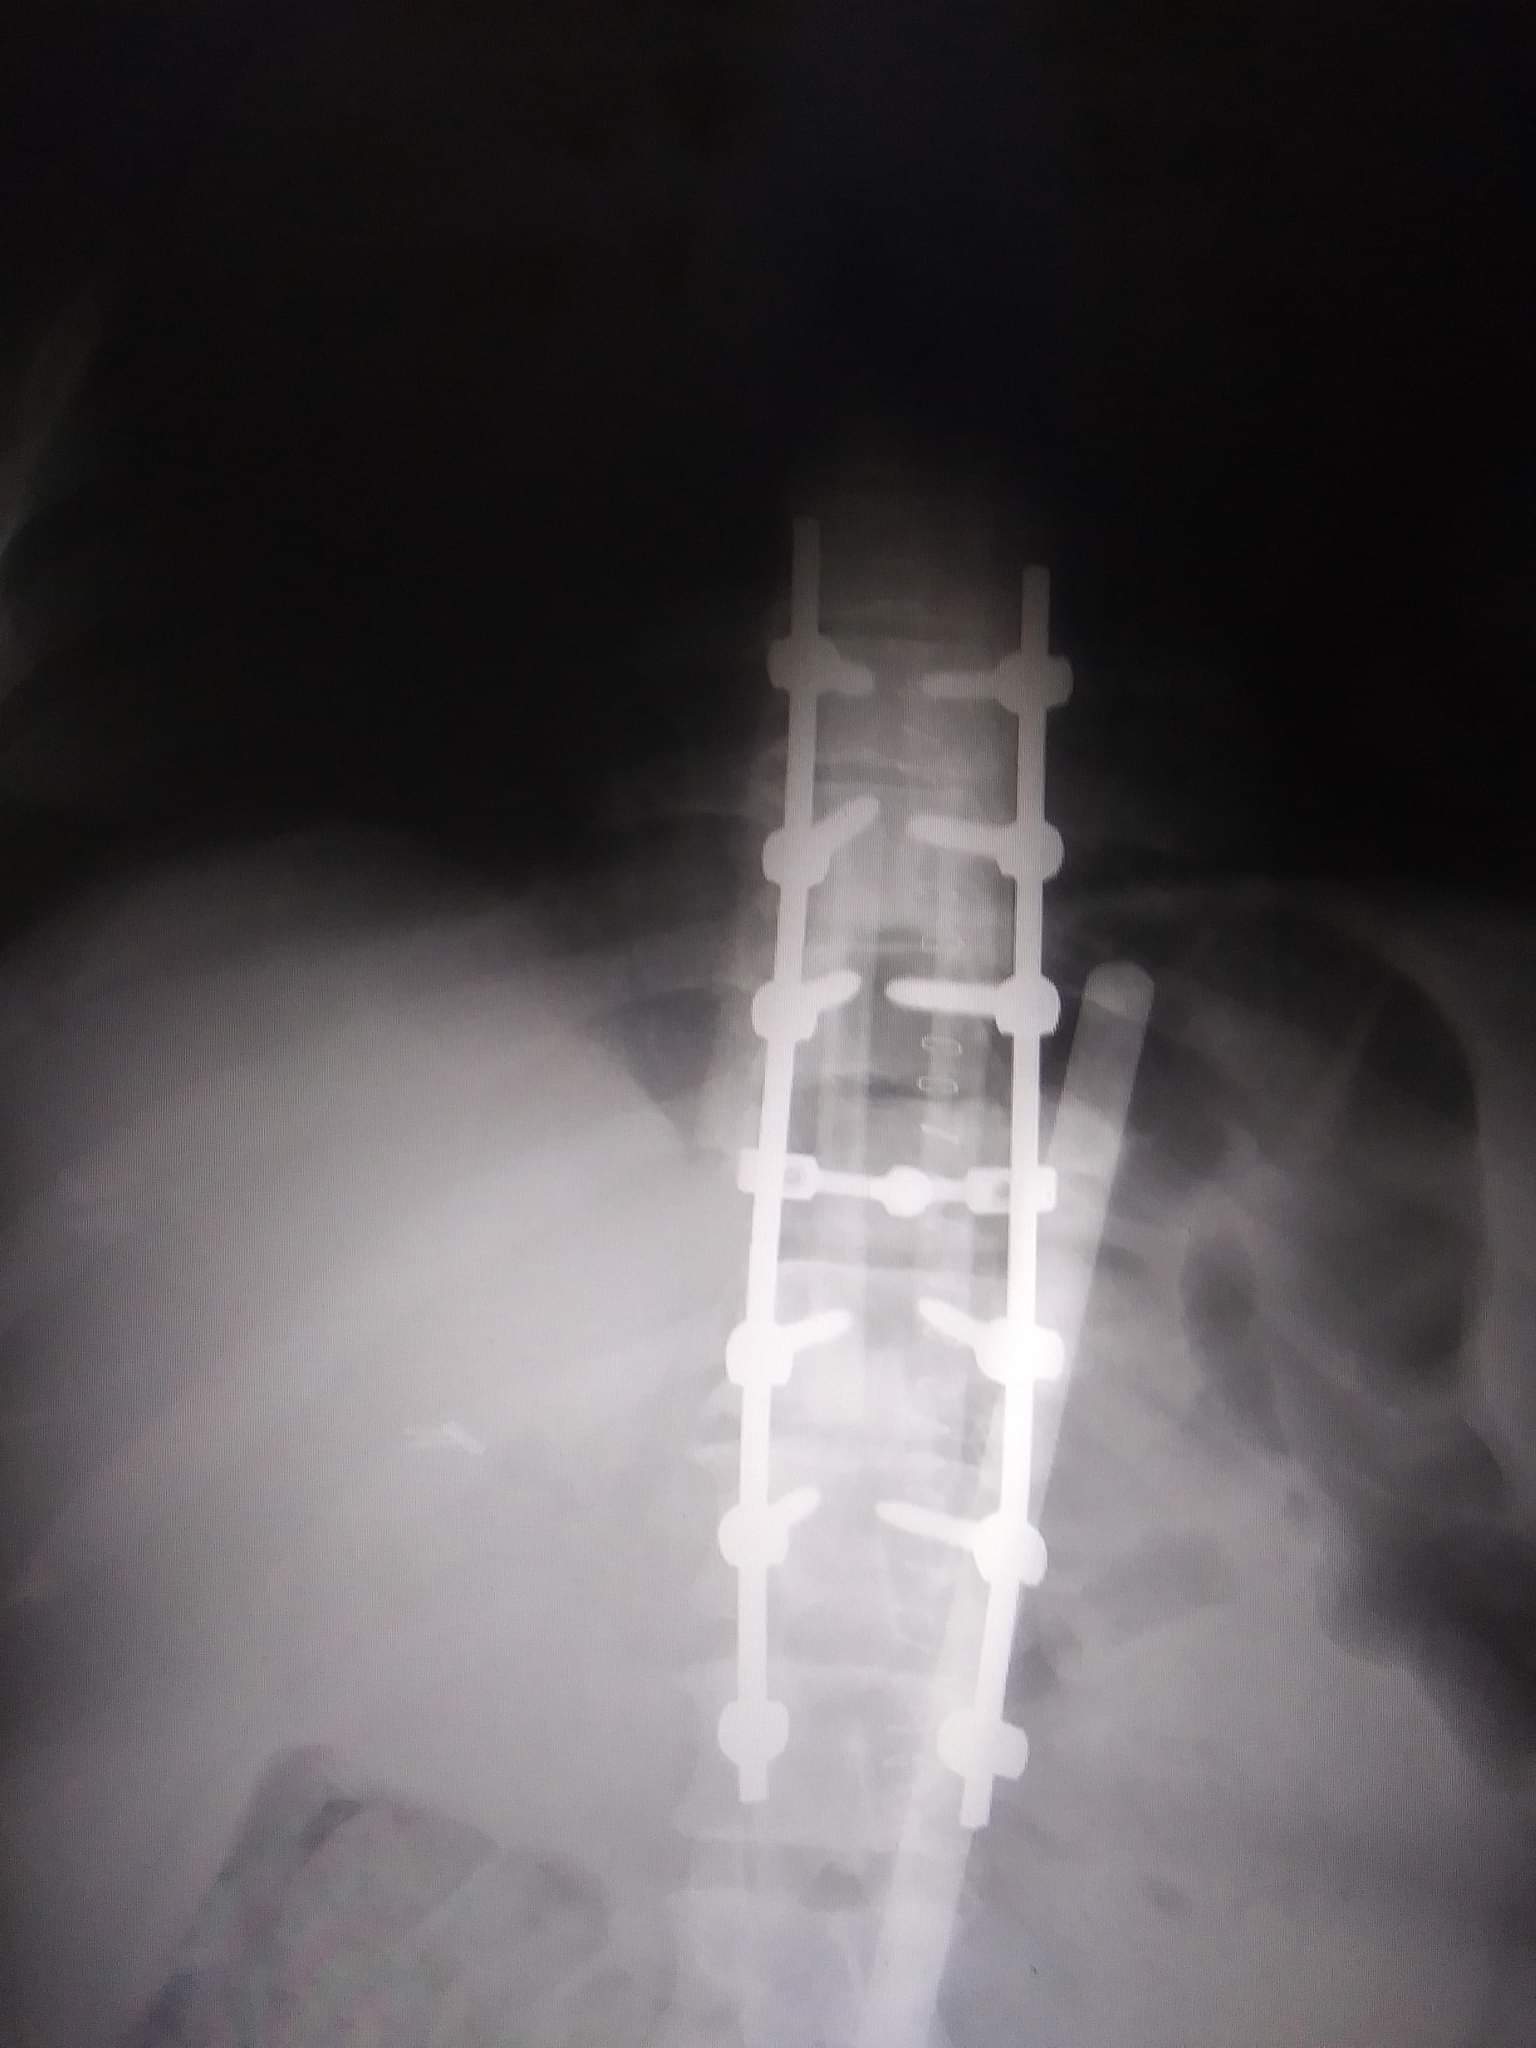

12/29/202” I got up like any regular day got my kids off to school all pets and outside animals fed got ready and headed to work as I was going up the hill I I hit a patch of black ice and I knew I was not going to recover I took my hands off the wheel covered my head and started praying I could here every thing crashing around I kept my arms wrapped around my head and kept praying I just kept getting colder until I hit something I didn’t know where I was I didn’t open my eyes I kept praying “god please don’t let the pickup land on me please lord my babies need me please lord” and then I heard the crash I cougar the engine still running so I felt around with my hands and felt snow I opened my eyes and my back hurt so bad I felt like I had a ball under me And I couldn’t feel my legs I knew instantly I broke my back I saw the pickup landed a way away it took me a minute to get myself together and remember I had my phone in my bra I called 911 we were on the phone over a hour they couldn’t find me!! I managed to tip my head and saw a familiar house once I told them I couldn’t see it they found me about 30 min later I remember a huge relief come over me because I heard “o my got DONT move sweetheart were here we got you “ then Our neighbor Everet and the sheriff came down the hill they hit their knees beside me and grabbed my hands I remember they took off their coats and laid them over me and kept telling me “the ambulance is almost here hold on sweetheart” I heard the sirens then a bunch of people were around me and working fast it scared me and my anxiety went sky high the one paramedic said “ we’re going to get you on the board get you up to the ambulance and get you a little something to help with the pain “ I was drowsy so I don’t remember much after that until I woke up the next morning of the 30th my sister was there she said when they took me to surgery based off X-rays I had a 10% chance to survive surgery once in there they told her it was much worse than they thought and they didn’t know if I would even make it but they were going to try their best the surgery was estimated to be 3 hrs it was almost 9 I woke up the next morning intimated and freaking out the dr came in and told me” I’m sorry I couldn’t save your legs I did everything I could but I couldn’t do it but I did make sure you made it” I spent the next 7 days in insane amount of pain and getting fitted for a brace it was all so much all so overwhelming! My kids were with my mom and not being able to see them!! On 1/7/2021 they transferred me to a rehab in Lincoln where I learned the basics for my own care I was supposed to be there until April 10th however I worked and worked and surpassed all my therapy goals and was discharged 2/13/2021 it took a few weeks to get used to being home and I was able to have the kids come home! Since then I have battles a few UTI’s one of wich landed me in the hospital for 9 days and due to the fact we live in the country and don’t have appropriate transportation for me I can’t get to drs stores therapy or any events with my kids or family without therapy I have done the best I can but my flexibility has suffered and it’s harder to move my legs! my depression anxiety and independence has suffered so much I used to be so active went lots of places as a family tan errands always helping someone who needed it between the kids the 5 dogs the 39 birds I had a lot of outside work cooking and baking goodies NOW I don’t have my birds anymore I can’t get around outside I only have a manual chair and it’s all sand out here so I don’t go far I am not able to do all the cooking and baking and definitely can’t do any of my outside stuff ! I don’t get to go to stores or go shopping or go have a meal with anyone I do what I can I might have to Adapt how I do things but I can do nearly 1/4 of what I could before I was kicked off 2 programs for home health because I can’t find my own provider(still on one program just don’t have a provider)so I literally depend on my kids for a lot and basic housework takes so much out of me especially since I am not taking any narcotics for pain I haven’t since July. My best friend is a contractor and we bought the material and he built me a deck and ramp I don’t have access to my bathroom because it’s not setup for me and it’s not big enough the way it is I either do a “sponge bath” and occasionally I will go to my moms in alliace to shower but that’s only about once every few months. I have some material for my bathroom but besides the bathroom we have to redo the floors because the carpet is hard for me to roll on because of the high padding and our floor in dining/living room is crappy and sometimes my wheels get stuck on them so makes it tough on me.